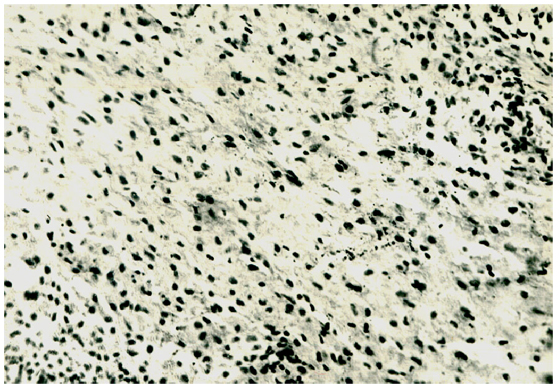

Рис. 1. Гистологическая картина эндометрия при ХНСО

Секреторные изменения также не были характерными для второй фазы менструального цикла (рис. 1), и в этих случаях обязательным был воспалительный фон. Даже ЖГЭ (в 5,6%) сопровождалась последним.

При гистологическом исследовании эндометрия на фоне выраженных изменений воспалительного характера с высокой частотой выявлялись умеренная пролиферация, гипоплазия эндометрия и отсутствие секреторных превращений во вторую фазу менструального цикла.